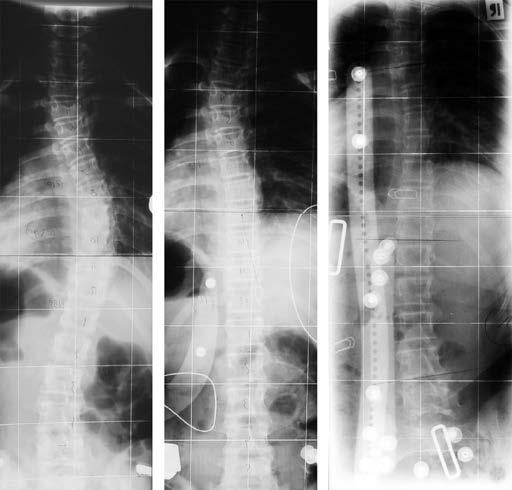

Abbildung 150: Verlauf einer idiopathischen Adoleszentenskoliose bei einem Jungen mit 56 Grad zu Beginn der Behandlung im Wachstumsalter. Am Ende ist die Krümmung im Röntgenbild verringert, deutlich kompensiert und klinisch kaum mehr zu sehen (aus: Weiss und Moramarco 2013).

Abbildung 158: Elfjährige mit idiopathischer Skoliose im Verlauf der Behandlung während des Hauptwachstumsschubs. Die Oberflächenvermessung und das Röntgenbild können verglichen werden. Nach zweijähriger Behandlung (c und d) erscheint der Rumpf des Mädchens bereits relativ symmetrisch und die Krümmung hat sich von 38 Grad Cobb (links) auf 19 Grad (rechts) verbessert.